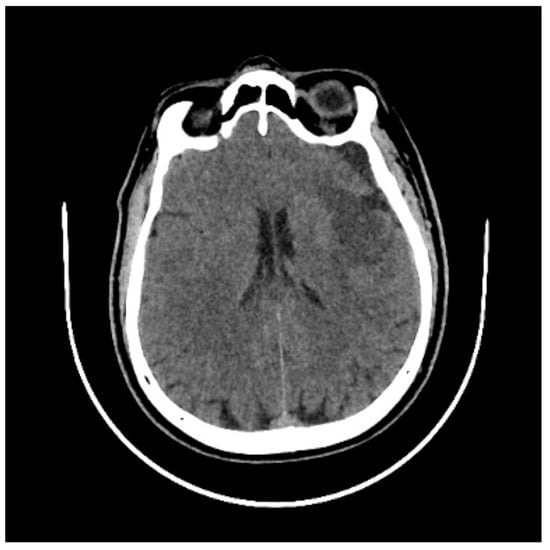

2. Case History